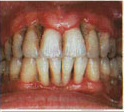

Stage 4

Advanced Periodontitis in which bone loss is severe causing mobility of teeth and gingival recession.